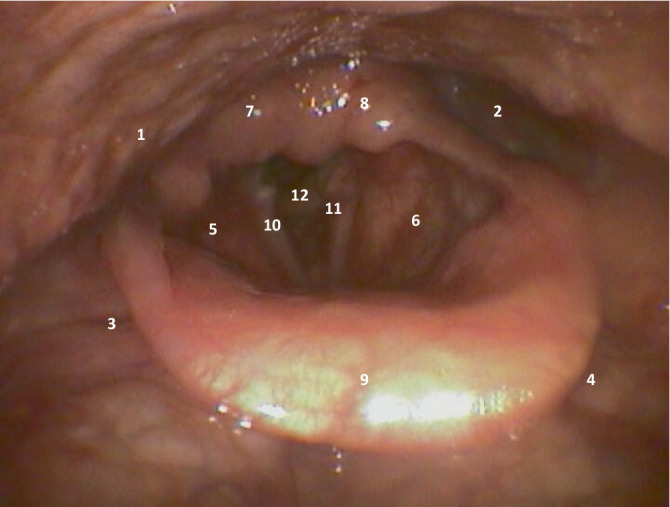

Postextubation dysphagia (PED) is common in intensive care units (ICU), affecting about 20% of patients of mixed medical surgical ICU populations. PED is an independent risk factor for increased 28-day and 90-day mortality in both neurological and nonneurological ICU patients (28-day mortality: plus 9%). The increased mortacity risk can be demonstrated for up to approximately one year after the ICU stay. Due to the consequences of PED, all ICU patients should undergo systematic dysphagia screening after extubation/decannulation (e.g., water swallow test) and fiberoptic endoscopic evaluation of the swallowing (FEES) to confirm the diagnosis. Treatment is interdisciplinary with nutrition adaptation/nutrition introduction or food restriction, physical/speech therapy and, if necessary, interventional procedures in the future.